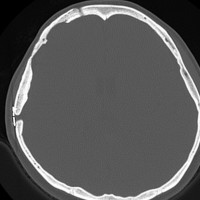

骨内髄膜腫 osseous meningioma

骨内増殖をする髄膜腫です。頭蓋骨腫瘍と間違えるようなものです。触った感じは骨腫ですが,CTでは,表面が毛羽立っていて,頭蓋冠に浸潤していることが特徴です。浅側頭動脈からの豊富な血流があります。

わずかですが頭蓋内にも腫瘍があり,硬膜が肥厚してガドリニウム増強されます。

頭蓋骨をかなり広範におかすので骨は捨てません。開頭して取り外した骨の厚くなっている部分と髄膜腫で軟らかくなっている部分を削除して,それから骨片をオートクレーブで短時間熱処理して,元あった所にもどします。下の画像は手術後1年半が経過したものですが,髄膜腫の再発はなく,熱処理骨弁は吸収されないで生着しています。